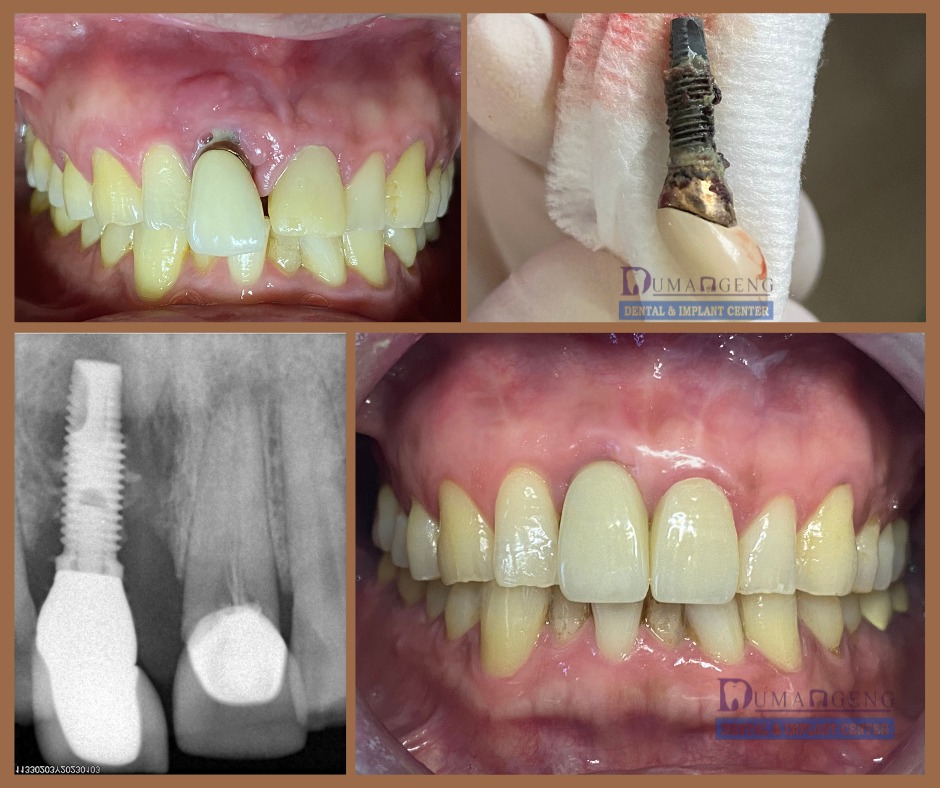

From Severe Infection to a Radiant Smile!

We’re thrilled to share this transformative journey at Dumangeng Dental and Implant Center!

A patient came to us with severe peri-implantitis, a serious infection threatening their dental implant and surrounding bone. Our expert team sprang into action:

Removed the infected implant

Performed precision bone grafting to regenerate lost tissue

Placed a brand-new implant with advanced techniques

The results? Perfectly healthy gums, natural-looking crowns, and a smile that speaks volumes. Our patient couldn’t be happier with their restored function and confidence.